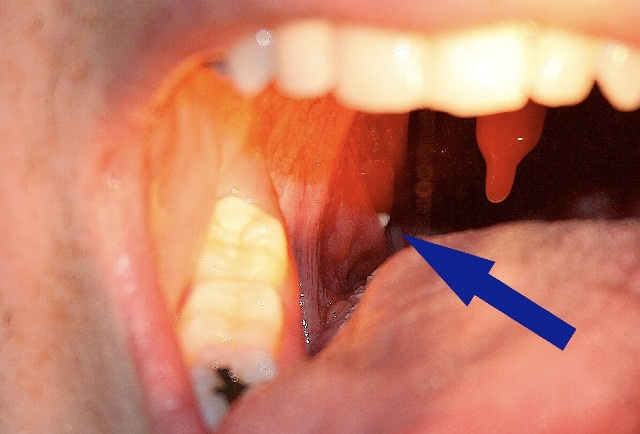

دانههایی روی لوزهها

به طور کلی، التهاب سبب تورم لوزهها میشود. لوزهها معمولاً به رنگ قرمز روشن درمیآیند و بزرگتر از حد نرمال میشوند. لوزهها ممکن است پوششی از لکههای سفیدرنگ یا زردرنگ داشته باشند.